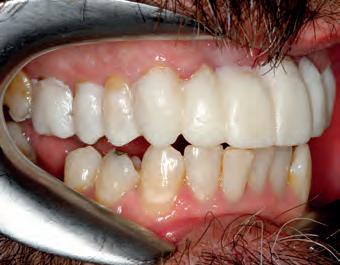

TOP ROW: Before lower occlusal, Before retracted in occlusion 2ND ROW: Before retracted left in occlusion, Before retracted left open 3RD ROW: Before retracted open, Before retracted right in occlusion 4TH ROW: Before retracted right open, Before upper occlusal

In our case, the patient decided in the on a bridge UR3 - UL3, bridge UL4-UL6 and a crown UR6. The patient was going to whiten the lower arch with Enlighten, for guaranteed B1 and less contrast with the new upper arch.

Cementation was done with Rely X Ultimate (clear, dual cure). No adjustment the occlusion was required, and the patient has been invited to return for a final check whilst not numb. Hence, only a limited amount of photos were taken post-op. The final photos are yet to be taken, however, the patient was very pleased to get his new teeth in time before Christmas.

PICTURED RIGHT TOP: Restorations on model front below 2ND ROW LEFT: Restorations on model occlusal 2ND ROW RIGHT: Immediate post OP smile Immediate post OP face